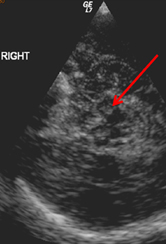

Zahlreiche Studien, unter anderem auch aus Innsbruck, belegen, dass viele Parkinson-Patient:innen schon vor dem Auftreten der ersten motorischen Symptome andere Dysfunktionen entwickeln. Im Frühstadium werden etwa die chronische Obstipation (Verstopfung), aber auch Stimmungsstörungen mit Depressivität oder Panikattacken beobachtet. Aber auch die Störung des Geruchssinns und die nächtliche REM-Schlafstörung können frühe Indikatoren für das Parkinson-Syndrom sein. „Mindestens 50 Prozent der Patient:innen zeigen bis zehn Jahre vor Beginn der Krankheit derartige Symptome“, bestätigt Prof. Poewe ein Forschungsergebnis aus einer, in Zusammenarbeit mit Forscherkolleg:innen in Barcelona durchgeführten Untersuchung. Die „prämotorische“ Phase kann Monate bis Jahre in Anspruch nehmen und bildet somit ein wichtiges Zeitfenster für die Frühdiagnostik. Diagnostisches Potenzial liegt aber auch in der Bildgebung: So konnte in mehreren Studien die prädiktive Relevanz von Ultraschallmerkmalen im Mittelhirn bestätigt werden.